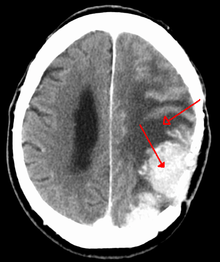

A contrast-enhanced CT scan of the brain, demonstrating the appearance of a meningioma

Meningiomas are visualized readily with contrast CT, MRI with gadolinium,[14] and arteriography, all attributed to the fact that meningiomas are extra-axial and vascularized. CSF protein usually is elevated if lumbar puncture is attempted.